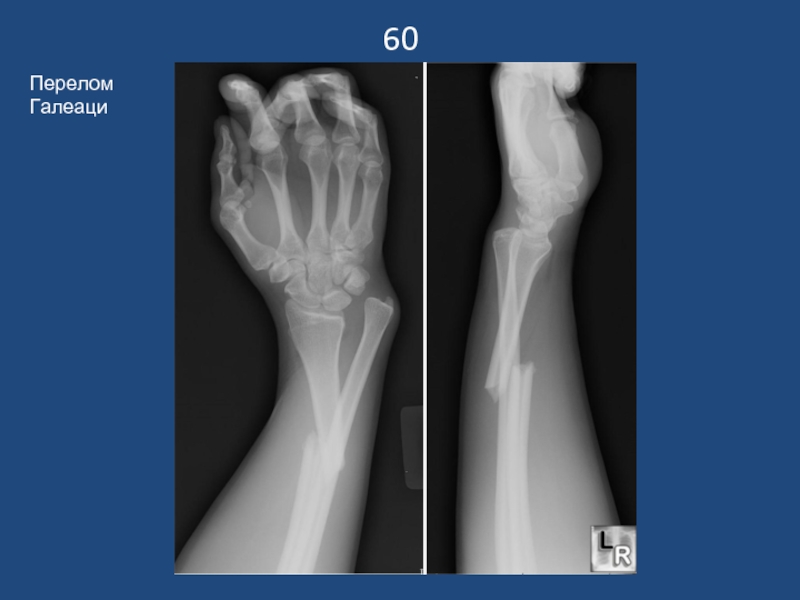

Слайд 6160

Перелом Галеаци